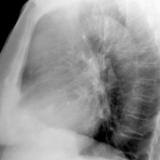

Case 9 Thymoma Lat

Date: 04/04/2010

Views: 3260